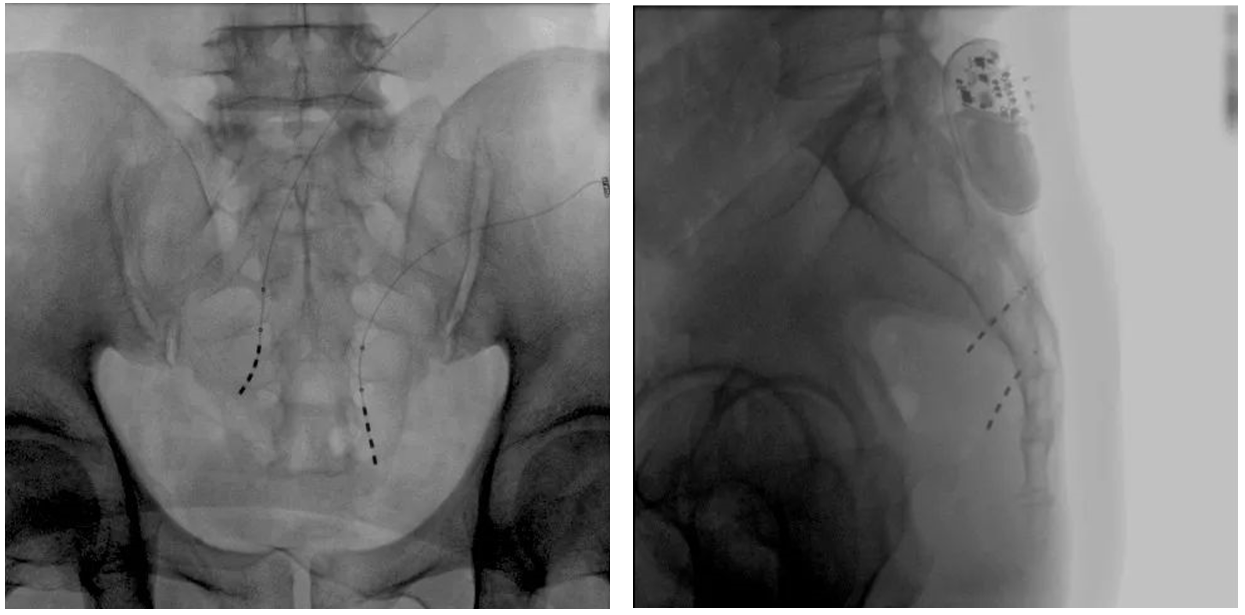

大平板一體式移動C形臂術中影像

在骶神經調控術或者骶神經刺激術(SNS)中,醫師首先會在透視引導下把電極通過導針插入到骶3神經孔位置,通過脈沖電流的刺激,達到興奮神經纖維并抑制逼尿肌收縮。在這一步,醫師會先對患者的神經刺激反應做測試評估,如果刺激效果明顯,說明該方案能夠達到手術預期。接下來醫師會在附近皮下脂肪處植入一塊脈沖電流發生器并與電極相連,使該部位今后能得到長期的電刺激,改善OAB癥狀。

? 傳統9英寸的平板探測器或影像增強器C形臂,成像范圍較小,在進行導絲定位觀察時,受手術床的限制無法呈現大視野的透視圖像,需要進行多次的拍攝,降低手術的效率。而普愛醫療大平板一體式移動C形臂裝備一塊30cm x 30cm大平板探測器,超大的成像區域彌補了因擺位不便造成的拍攝困難。

? 相較于影增C形臂,平板探測器成像的畸變更少,能夠準確體現電極和骶孔位置關系,提高手術效果預期。